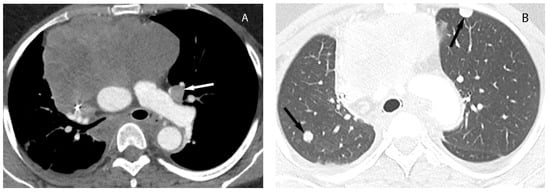

Visceral (Middle) Compartment

8. Cystic Lesions

9. Hypervascular Lesions

10. Esophageal Lesions